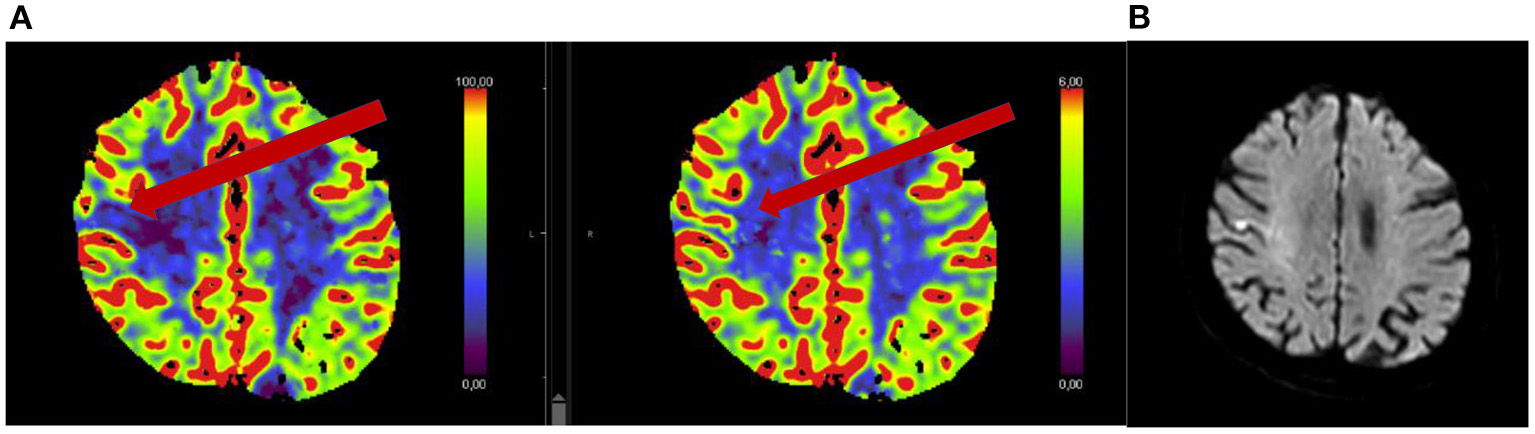

Thrombolysis for wake-up stroke with minor symptoms has not been specifically studied. As mentioned previously, many stroke centers do not perform advanced imaging in those with NIHSS ≤ 6, and may be missing those with mismatch deficits or large vessel occlusions who could potentially benefit from thrombolysis. See also illustrative patient case in Figure 2.

Figure 2. Seventy-five year old woman with acute onset of mild left hemi-body weakness and sensory loss (NIHSS 3). Patient received intravenous thrombolysis and showed clinical improvement. Acute CT perfusion showed a mismatch between normal cerebral blood volume (B) and reduced cerebral blood flow (A). Follow-up MRI performed 24 h after thrombolysis showed a small cortical ischemia.